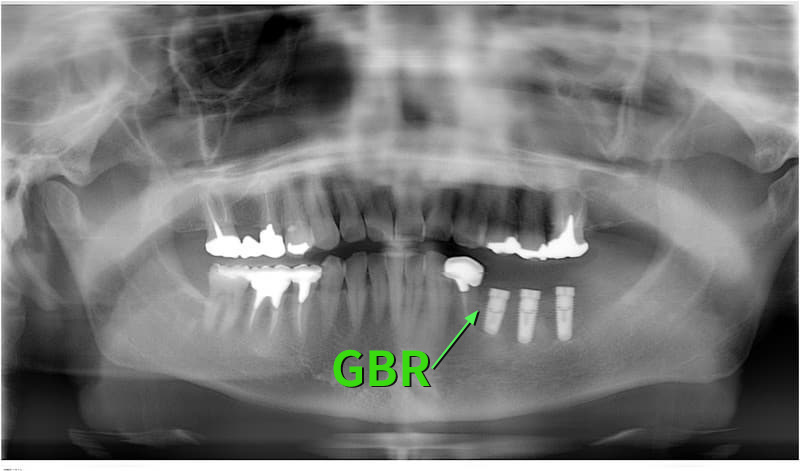

病歴や健康状態に関する問診、口の中の検査、レントゲン写真や歯型の採取

治療方針、計画の決定と説明

- 外科処置によって顎の骨にインプラントを埋め込みます。